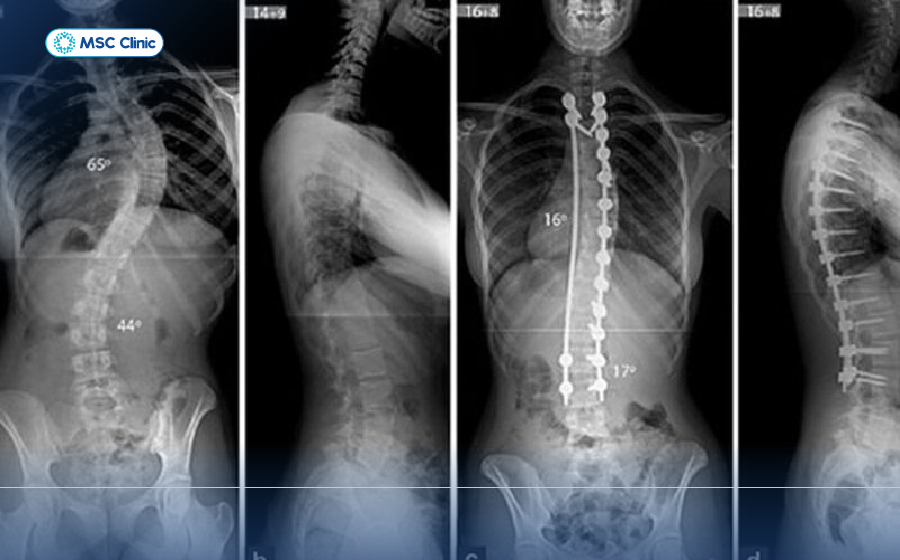

Hình ảnh cột sống trên phim chụp X-quang

Hệ thống máy X-quang kỹ thuật số mang lại hình ảnh rõ nét hỗ trợ bác sĩ chẩn đoán